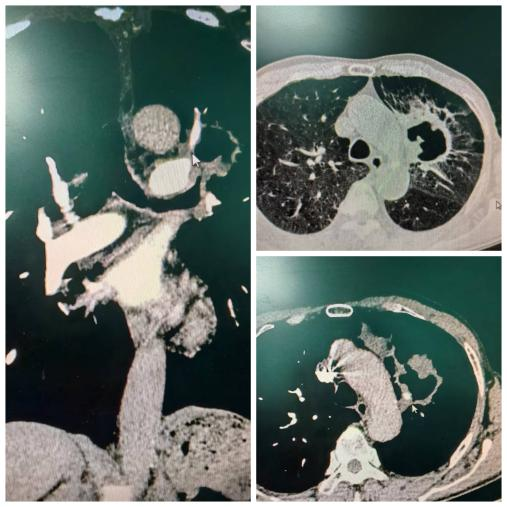

在这些所谓的“意外事件”发生之前,其实存在一些蛛丝马迹。肺动脉爆裂综合征(Pulmonary Arterial Blowout Syndrome, PABS)就是其中重要的一种。进展期肺癌导致的中央型肺动脉破裂,可瞬间导致窒息和休克,特称为肺动脉爆裂综合征。主要分为以下三种不同的类型:第一种是假性动脉瘤起源于中央型肺动脉(Central type of Pulmonary Artery, CPA);第二种是中央型肺动脉直接暴露于肿瘤空洞内;第三种是中央型肺动脉被肿瘤进行性坏死及小空洞包绕。如下图所示:

图2.增强CT示中央型肺癌伴空洞形成

图3.肺动脉造影图及血管塞栓塞肺动脉分支

当胸部CT发现肺部空洞性病变时,需要及时完善胸部增强CT检查,或者肺动脉CTA检查。评估空洞壁周围血管的情况显得至关重要,有助于及时发现肿瘤空洞内裸露的肺动脉。提前通过肺血管介入手段,采取弹簧圈或血管塞栓塞病灶内的责任血管,能够显著降低大咯血引起窒息的风险。